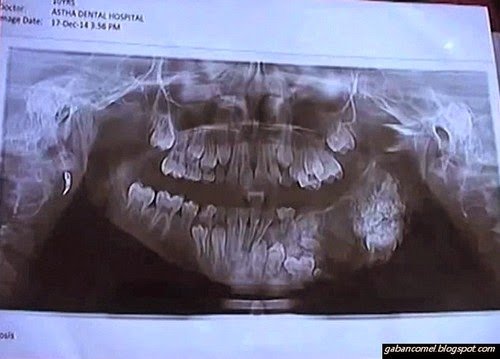

Tetapi apa yang anda fikirkan, jika anak berusia 7 tahun mempunyai lapan puluh gigi yang tumbuh di rahangnya? Tentunya itu bukan perkara yang menggembirakan. Bahkan boleh menyebabkan kesakitan yang luar biasa apabila mengunyah makanan.

Inilah yang dialami oleh seorang kanak-kanak di Mumbai, India. Kanak-kanak bernama Maharaja Yashwantrao ini didiagnosis mengalami penyakit bernama odotama, iaitu berupa ketumbuhan di gusinya yang menyebabkan giginya tumbuh banyak dan tidak normal.

“Pesakit tersebut datang kira-kira lima hari yang lalu, dengan aduan sakit pada gusinya. Dan selepas mendiagnosis, ia mengalami penyakit bernama odotoma. Kami merancang membedahnya. Dan mengeluarkan kira-kira 80 gigi,” kata doktor gigi di salah satu hospital di India.